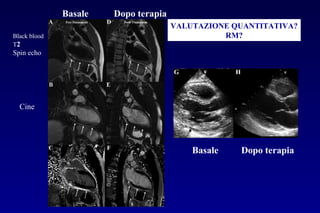

VALUTAZIONE QUANTITATIVA?

RM?

Basale Dopo terapia

Black blood

T2

Spin echo

Cine

VALUTAZIONE QUANTITATIVA? RM? Basale Dopoterapia Basale Dopo terapia Black blood T2 Spin echo Cine L.E.